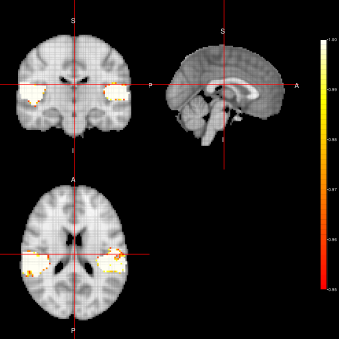

Figure 2: Activation Maps for the ”voice localizer” example obtained when using the FEST algorithm under three different distributions (Marginal, Joint and LTT) related to the state parameter.

From figures 2, 3 and 4, we can see the activation maps obtained for the ”voice localizer” experiment using the method proposed in this work. From those images, we can say that the three algorithms (FEST, FFBS and FSTS) under the three different distributions (Marginal, joint and LTT or average distribution) successfully identify the temporal activation due to voice and non-voice sounds stimulation, nevertheless there are some slight differences among those maps worth mentioning. For instance, the maps obtained when using the FFBS algortihm allows for the identification of a broader activated region from the temporal cortex, however, on the other hand, it allows activations to appear (false-positive activations) on brain regions that should not be involved with this ”voice localizer” experiment. On the other hand, more conservative results seem to be obtained when using FEST and FSTS algorithms, but with less false activations.